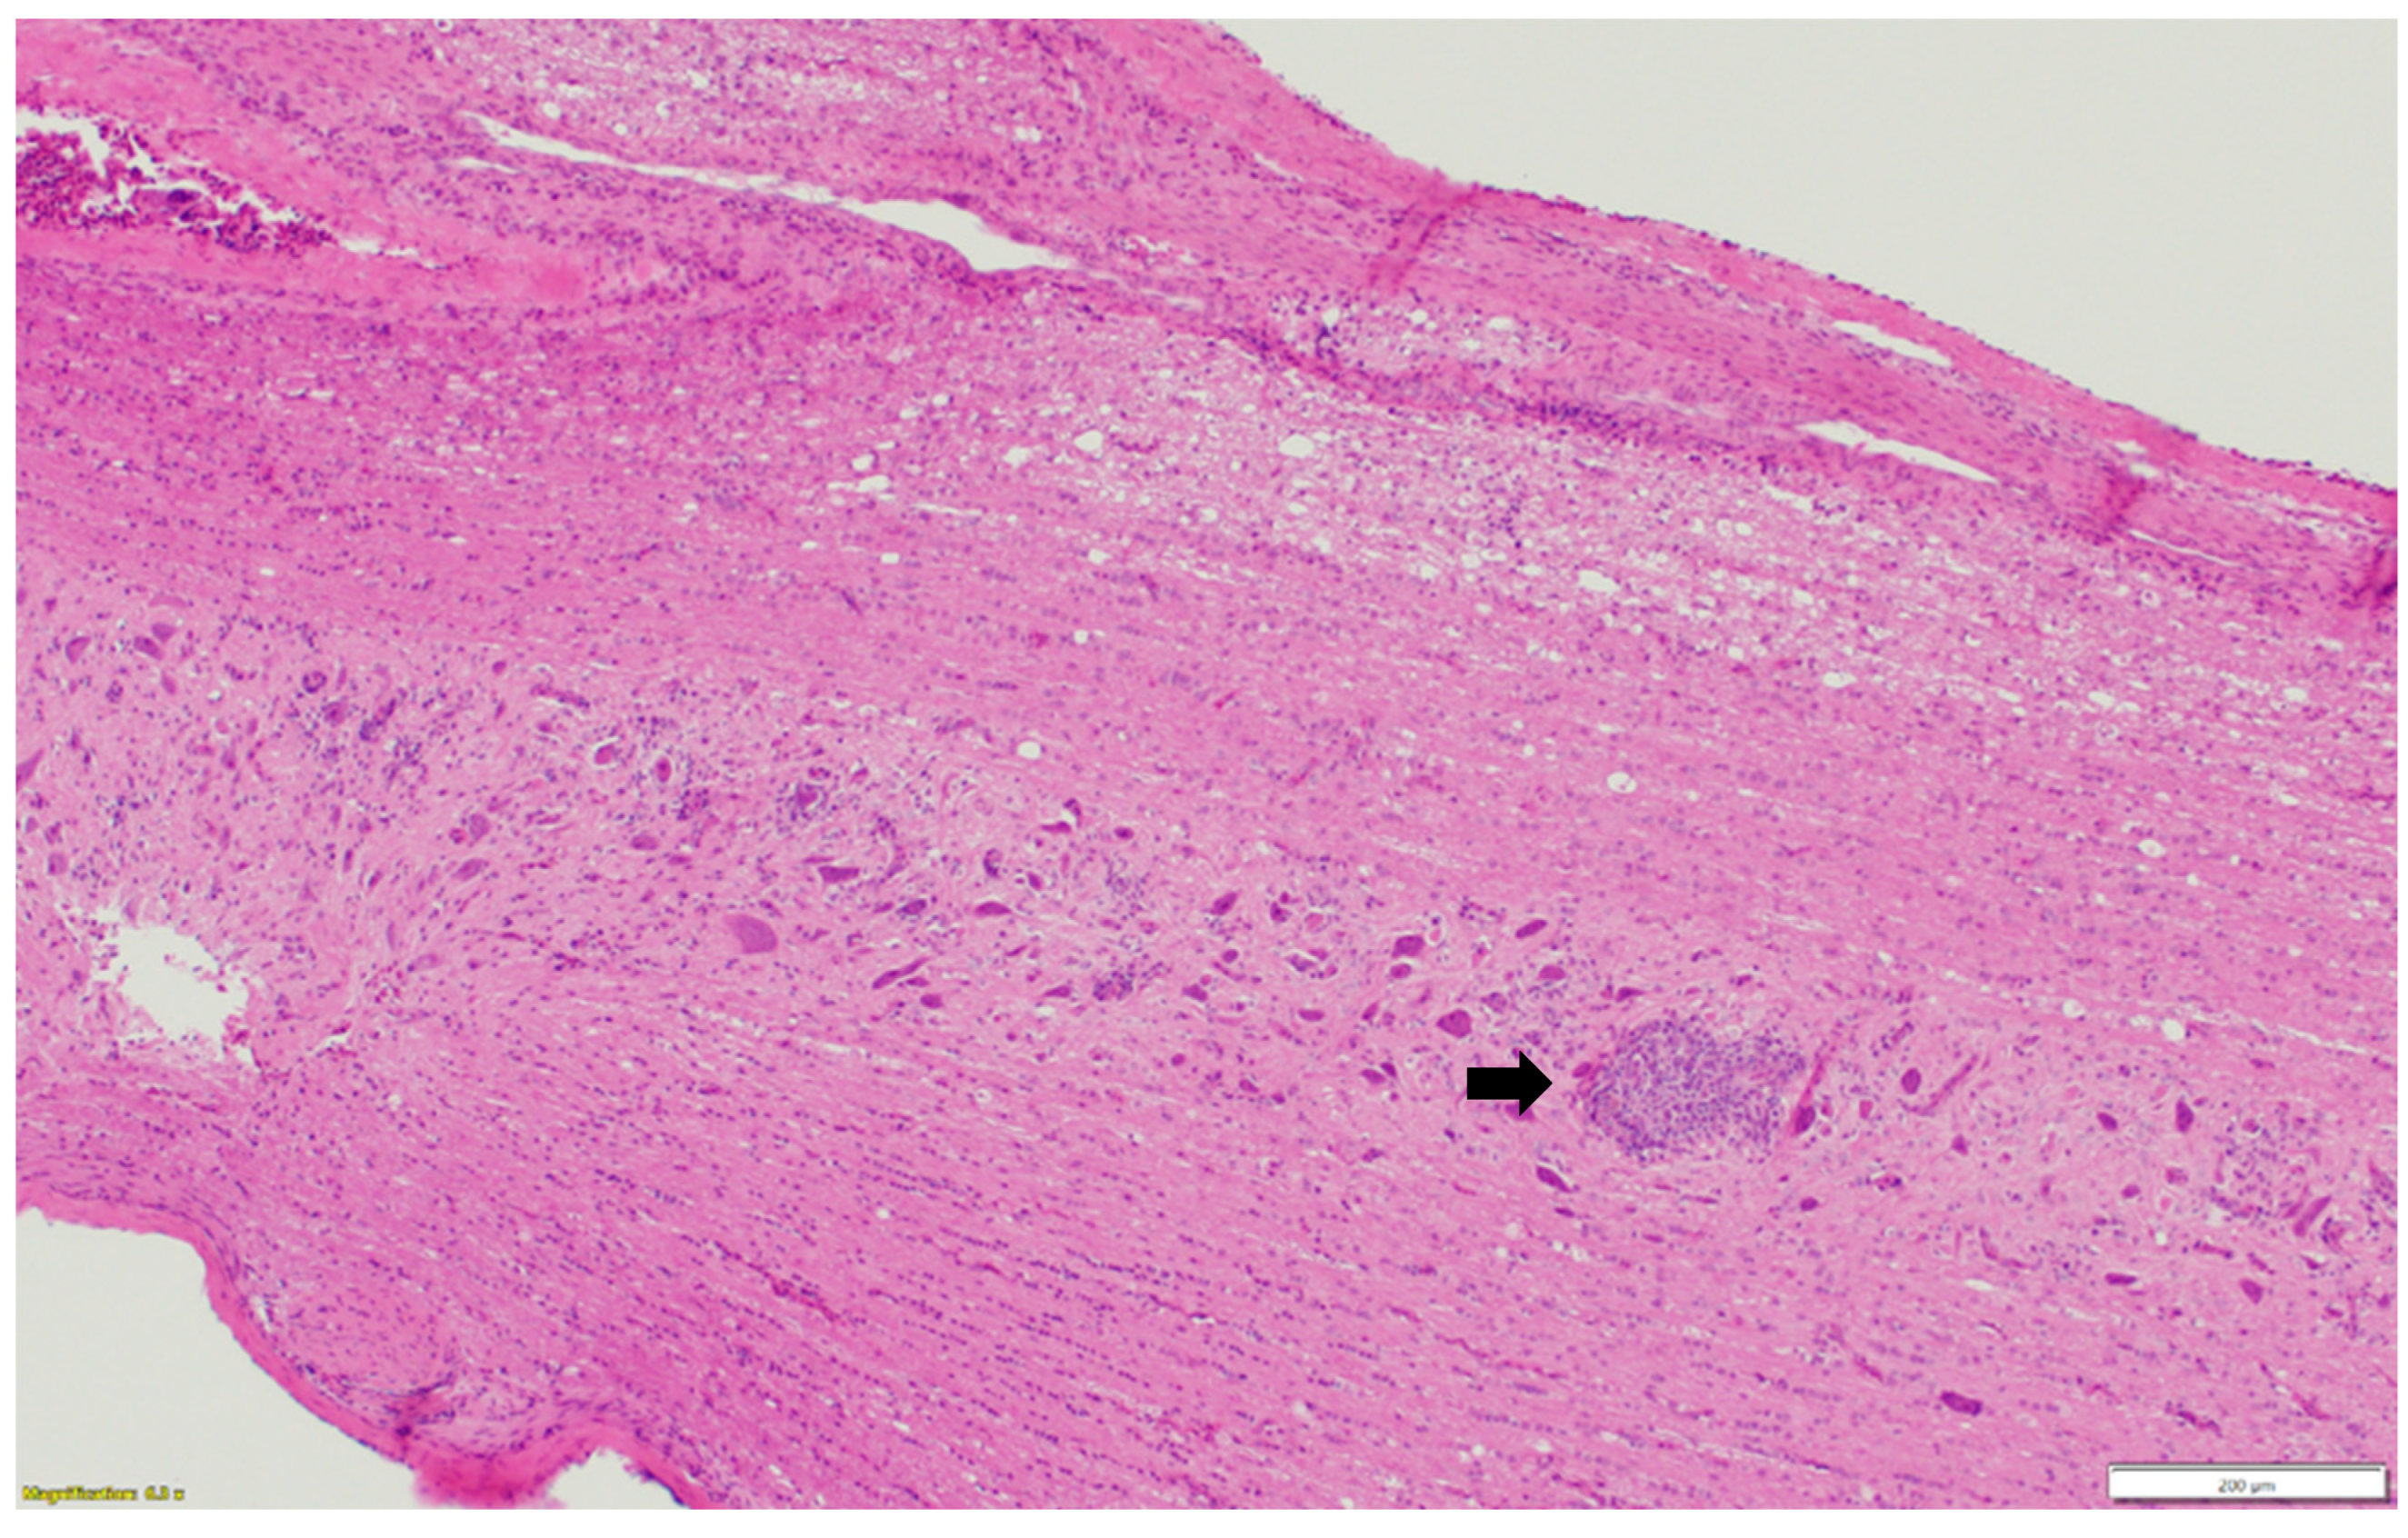

Microscopic examination of different brain, spinal cord, peripheral nerves, and ganglions sections revealed multifocal areas of lymphoplasmacytic and histiocytic infiltrates, indicating encephalitis (Figure 1) in the cerebral white matter, thalamus, hippocampus, and medulla oblongata close the ventricular space. The inflammatory cells around the vessels (perivascular cuffing) as well as around the neurons (satellitosis and neuronophagia) resulted in several neuronal degeneration and central chromatolysis (Figure 2). The gray matter in the spinal cord had multifocal lymphoplasmacytic infiltrates, indicating myelitis (Figure 3). In addition, there was mild to moderate multifocal ganglioneuritis in the pelvis ganglions (Figure 4).

Figure 3.

Multifocal lymphoplasmacytic infiltration (black arrow) in the gray matter of spinal cord. Paraffin-embedded tissue was stained with hematoxylin and eosin.